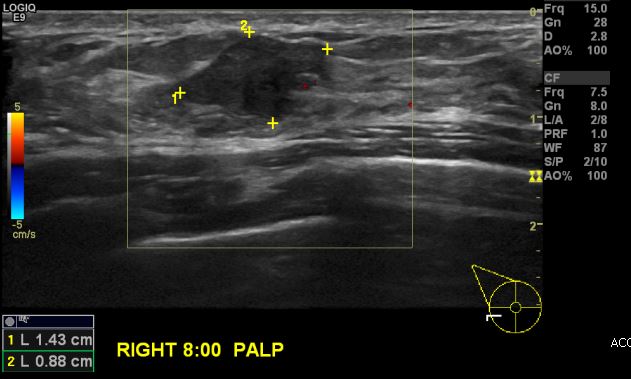

건강검진상 이상 소견으로 내원하신 40대 여성분으로 우측 8시 방향에 만져지는 혹 중앙핵생검 시행하여 우측 유관암 진단 되었습니다.